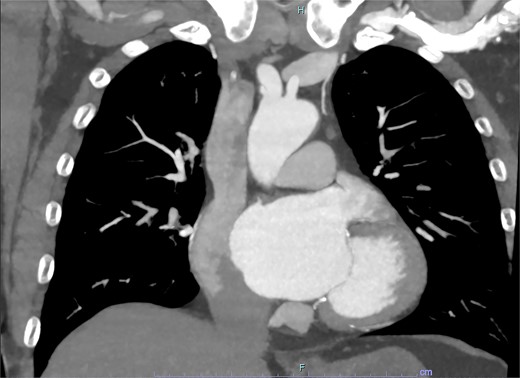

On arrive to the emergency department, the patient was found to be hypertensive with a blood pressure of 220/120 mmHg. Physical examination of the patient revealed no significant clinical findings. Serial troponins with corresponding ECG’s were undertaken which demonstrated no new evidence of myocardial ischaemia. Based upon the patient’s symptomatology, he underwent a CT aortogram which demonstrated a dissection arising from the proximal brachiocephalic artery. No dissection was noted in the ascending aorta, and there was no evidence of the brachiocephalic artery dissection extending into the subclavian or carotid arteries (Figs 1–3).

Coronal slice from CT aortogram demonstrating the origin of the dissection flap.